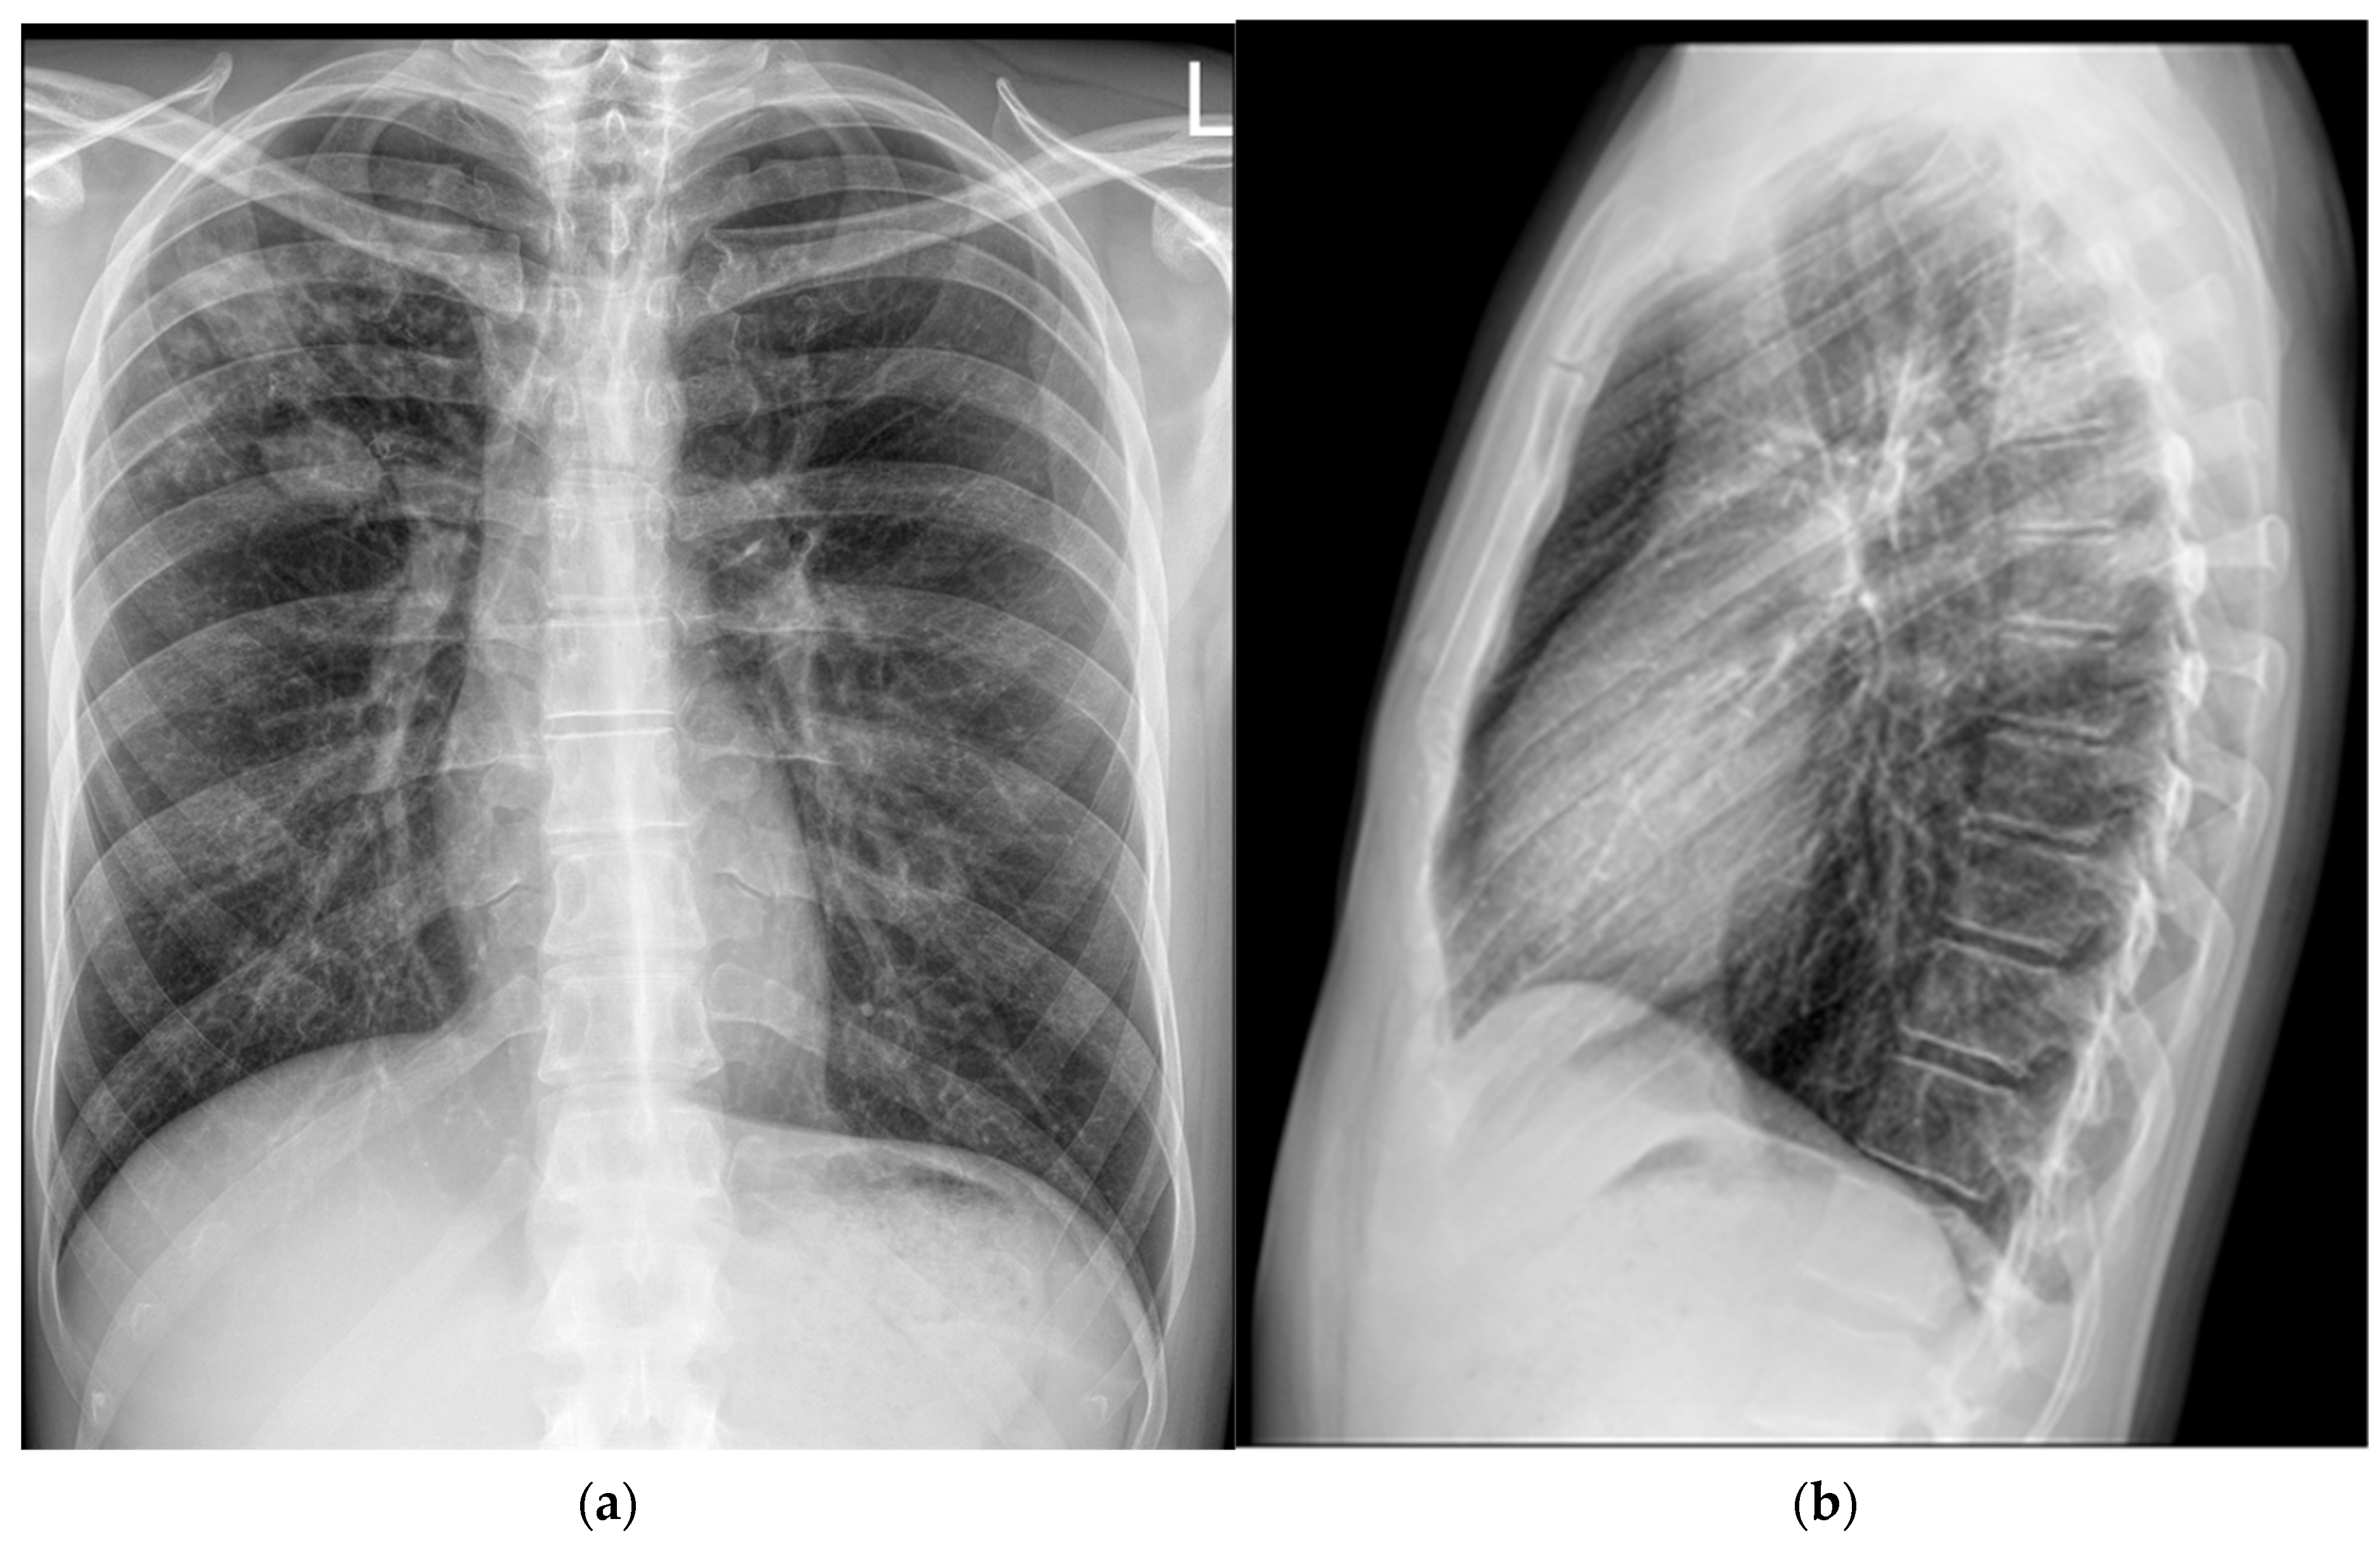

On 7 November 2024, a follow-up contrast-enhanced MSCT of the thorax was performed and compared with the previous CT scan from 29 April 2024 (Figure 4). It revealed several irregular, confluent solid lesions in the right apical region, the largest measuring 23 mm, 29 mm, and 20 mm in diameter, consistent with tuberculomas. Band-like fibrotic changes extending to subpleural and perifocal areas were also noted. In addition, micronodular interstitial changes and a “tree-in-bud” pattern were present, along with several solid parenchymal nodules up to 5 mm in diameter, suggestive of miliary tuberculomas. A tuberculoma measuring 26 × 26 mm was identified in the upper segment of the right lower lobe, with subpleural localization. Only a few reactive lymph nodes remained, with the largest measuring 9 mm in diameter.

Figure 4. Chest CT scans (7 November 2024): (a) solid lesions in upper lobe; (b) tuberculoma in the upper segment of the right lower lobe.